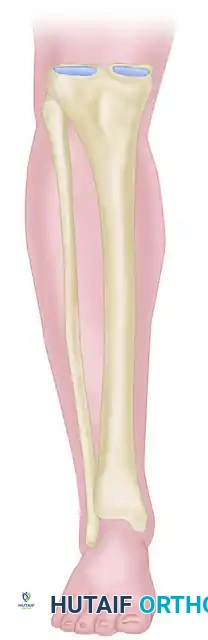

The Tibia

The tibia is the most common site for external fixation. The anteromedial face of the tibia is subcutaneous and represents the optimal "safe corridor" for pin insertion along its entire length.

* Proximal Tibia: Pins can be placed from medial to lateral or anterior to posterior. Avoid the common peroneal nerve laterally at the fibular neck.

* Middle and Distal Tibia: The anterior tibial artery and deep peroneal nerve lie closely applied to the interosseous membrane and the lateral cortex of the tibia. Pins must be placed strictly on the anteromedial surface.